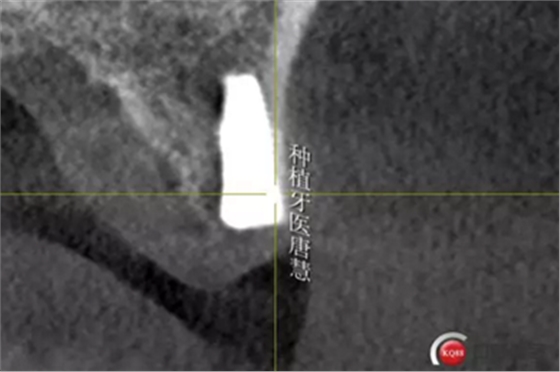

16牙槽骨條件尚好